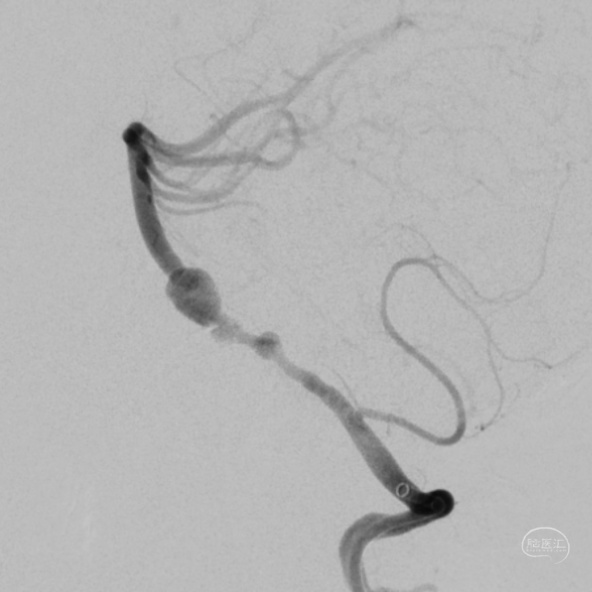

DSA:

3D重建显示基底动脉下部、双椎结合部、左椎多发夹层动脉瘤:

股动脉入路,置入8F长鞘,6F 115cm Navien™ 颅内支撑导管超选至左侧椎动脉V4段。

将Phenom™ 27微导管超选进入左侧大脑后动脉内,释放一枚3.25×35mm Pipeline™ Flex血流导向密网支架,远端定位在动脉瘤以远7mm,在动脉瘤处推密,近端定位在PICA起始部上端或远端,支架打开顺利。导引导管内推注替罗非班12mL,支架导管及微导管常规按摩,促进支架贴壁。